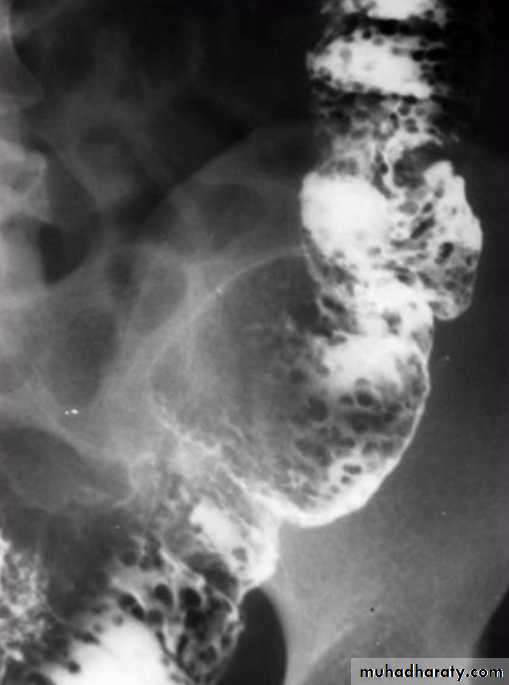

• Morphological types:• 1_ Ulcerative : give rise to irregularity of the colon with ulceration.

• 2_ Constrictive or infiltrative ( Annular ) type :

• a- Constant narrowing .

• b-Shouldering sign, apple core sign .

• c- Destruction of mucosa at narrow area .

• d- Double track due to fistula .

• e- In severe constriction ; stoppage of Ba. Flow with proximal dilatation .

3_Proliferative type : give rise to :

a- Large , constant filling defect with irregular margin .

b- Destruction of mucosa .

c- Intestinal obstruction

apple core lesion in the descending colon